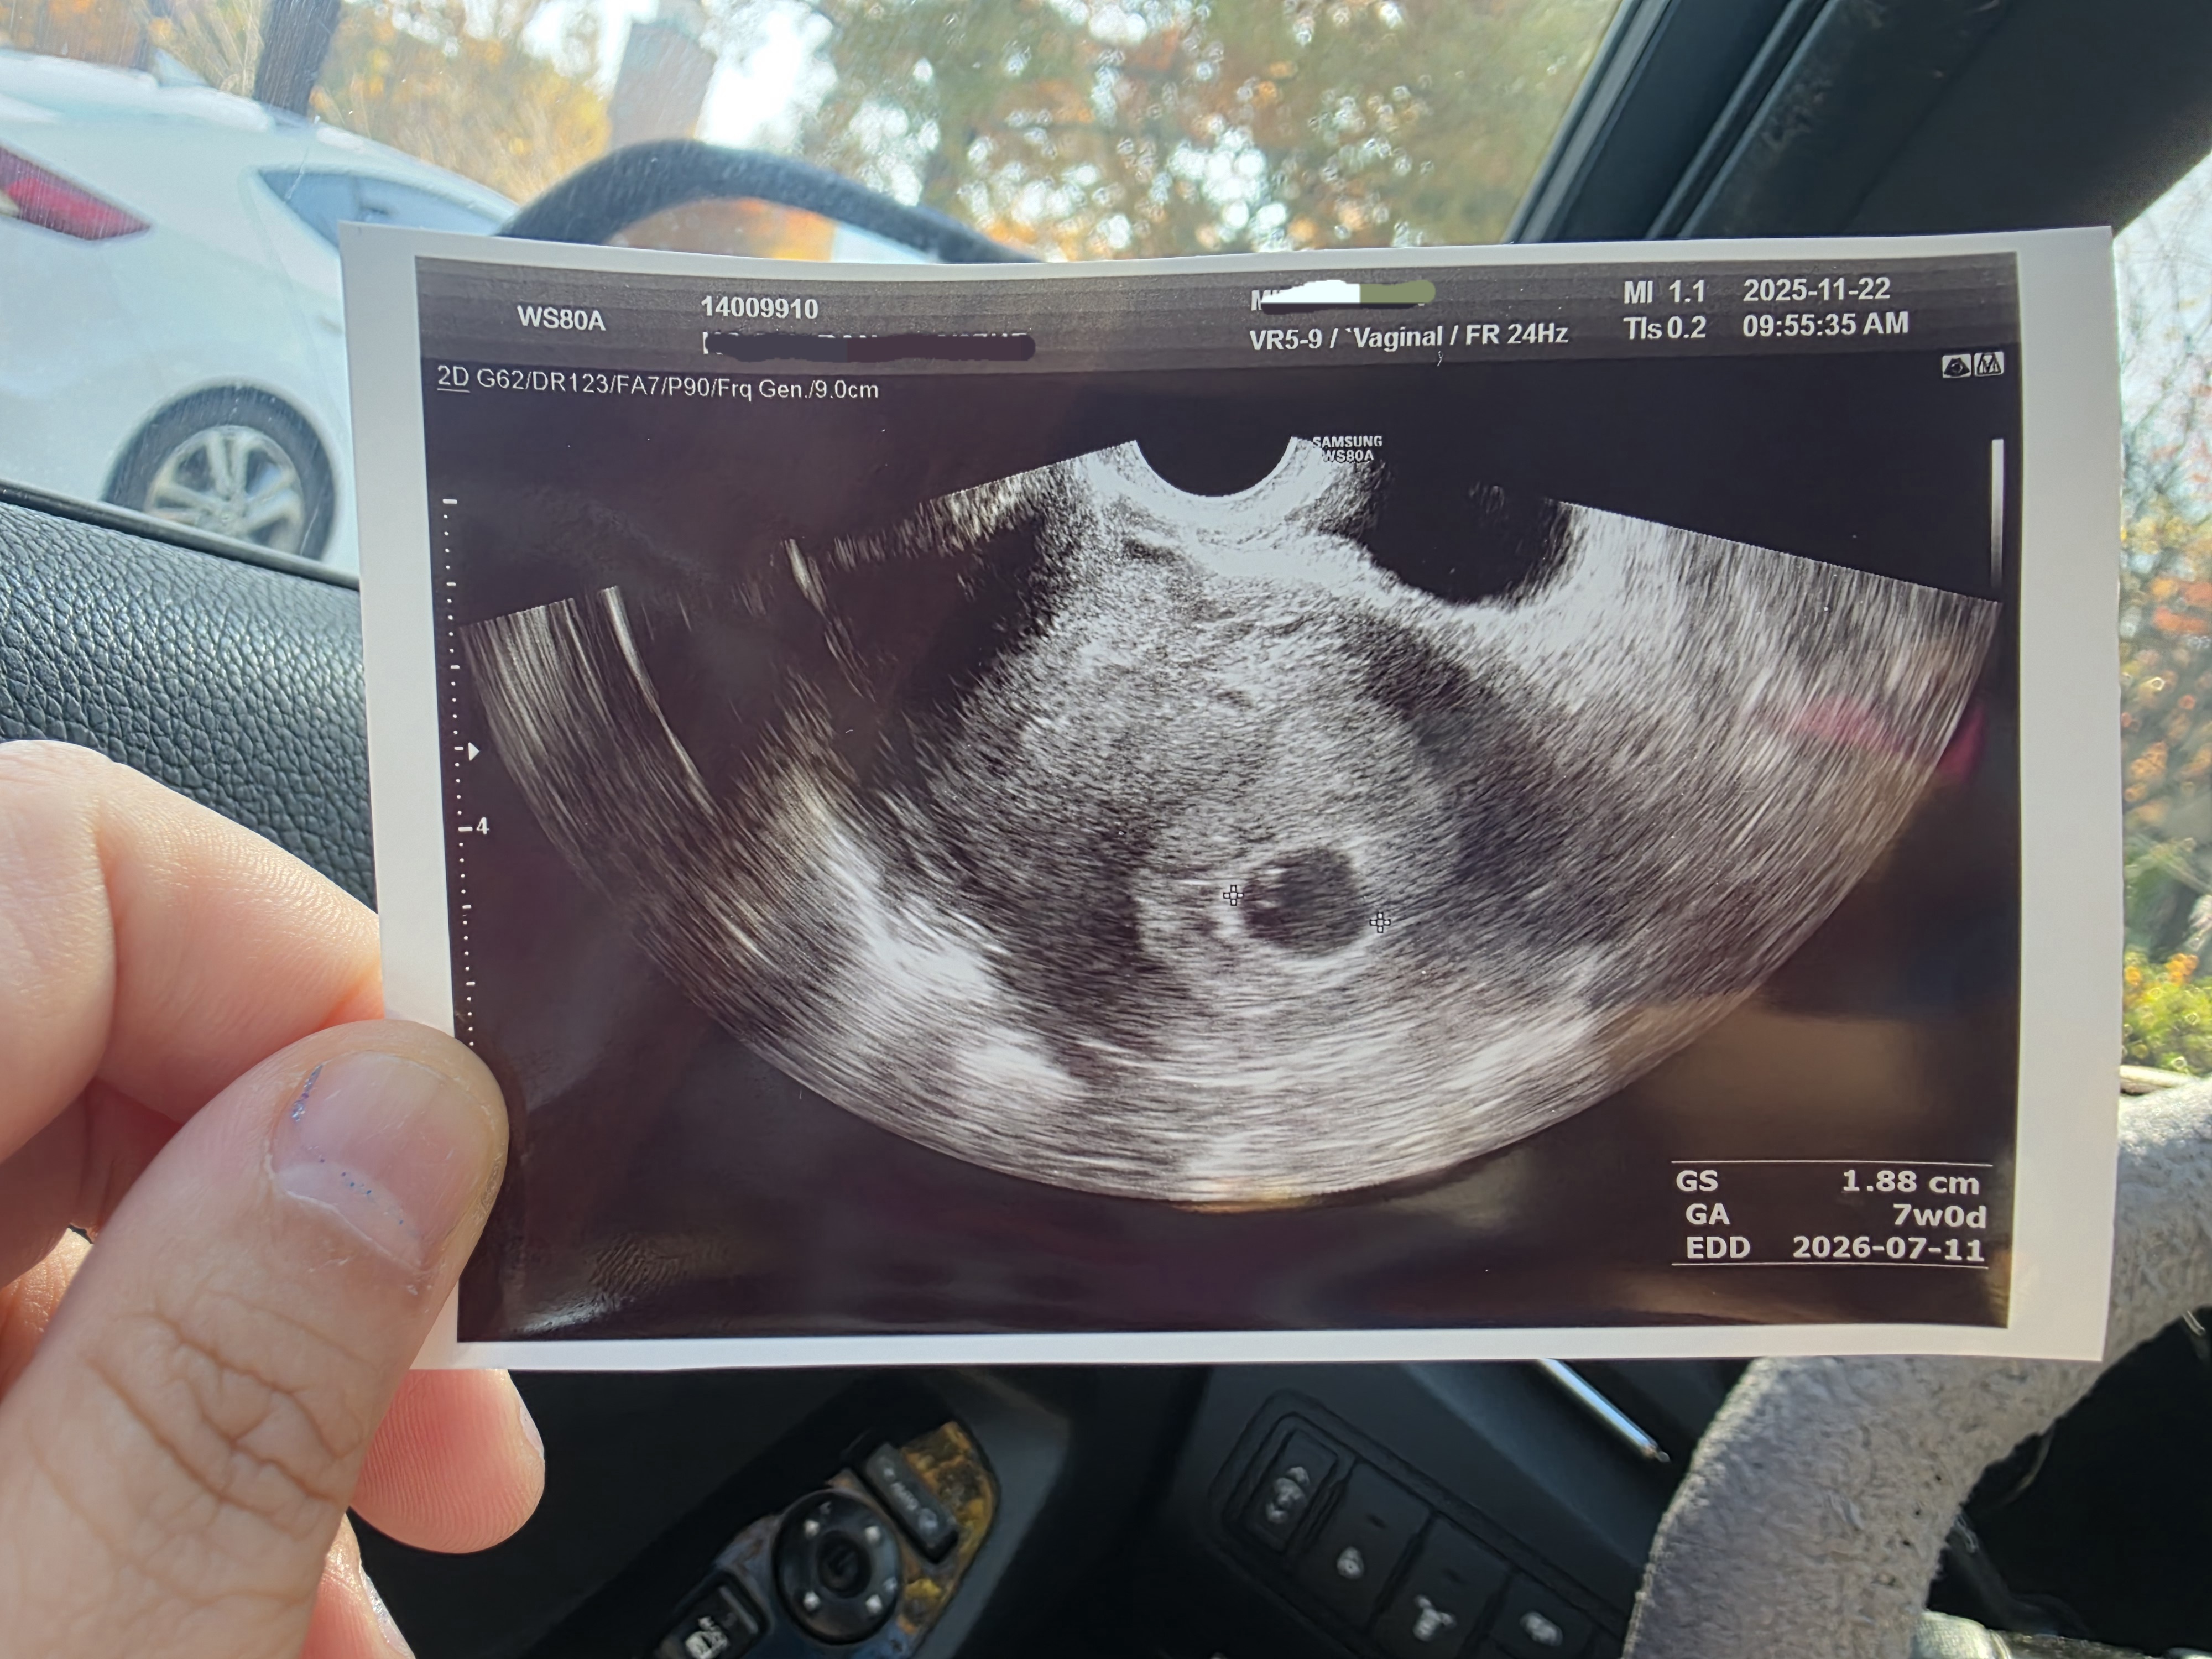

저번 주 토요일 22일에 아기집을 보고 왔어요~ 다낭성도 있고 당뇨도 있어서 아이 가지기 쉽지 않을 거라 생각했었는데 축복처럼 와 주어서 태명도 축복이로 지었답니다! 2주 뒤인 12월 5일에 병원 다시 가는데 잘 있나 너무 궁금해서 보러 가고 싶고 그래요 ㅎㅎ 아기집만 보아서 그런가 진짜 내가 품고 있나도 싶고 ㅎㅎ 우리 모두 파이팅입니다!